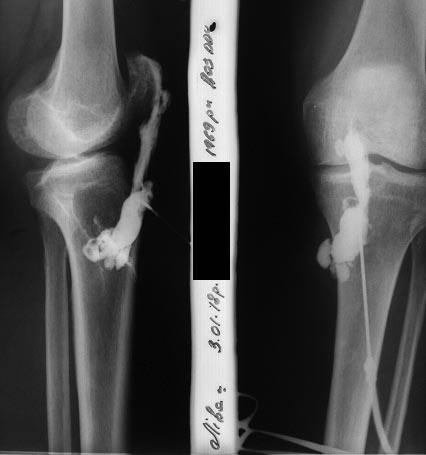

[Ortho] Остеомиелит надколенника

фистулография